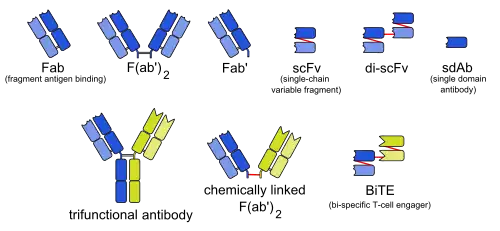

There are many formats of BsAbs, but the two main categories are IgG-like and non-IgG-like.[10] The main types of manufacturing methods are quadromas, chemical conjugation, and genetic recombination, and each method results in a unique format.[3][11]

This format retains the traditional monoclonal antibody (mAb) structure of two Fab arms and one Fc region, except the two Fab sites bind different antigens. The most common types are called trifunctional antibodies, as they have three unique binding sites on the antibody: the two Fab regions, and the Fc region. Each heavy and light chain pair is from a unique mAb. The Fc region made from the two heavy chains forms the third binding site. These BsAbs are often manufactured with the quadroma, or the hybrid hybridoma, method.[12][13][14]

Non-IgG-like

There are other BsAbs that lack an Fc region entirely, and thus leads to relatively simple design strategies.[1] These include chemically linked Fabs, consisting of only the Fab regions, and various types of bivalent and trivalent single-chain variable fragments (ScFvs). There are also fusion proteins mimicking the variable domains of two antibodies. The furthest developed of these newer formats are the bi-specific T-cell engagers (BiTEs), which uses the G4S linker to connect two ScFvs-one CD3 antibody ScFv and one tumor-associated antigen (TAA) or tumor-specific ScFv-to redirect T cells to cancer cells for target killing.[15][16][17] Other platforms include tetravalent antiparallel structure (TandAbs) and VH only (Bi-Nanobody). The TandAb platform is formed by a tetravalent antibody molecule containing two binding sites for each of two antigens.[18] In this platform, the reverse pairing of two peptide chains forms a homodimer molecule. As an example, AFM11 is based on the TandAbs platform and targets both CD3 and CD19 to achieve therapeutic effects. AFM11 showed dose-dependent inhibition of Raji tumors in vivo.[19] The Bi-Nanobody platform forms multi-specific binding through the connection between the VH regions of two or more antibody molecules. The products that are designed based on this platform are small molecules and these small molecules have high stability and better tissue permeability in vivo.[20] Even though non-IgG-like BsAbs have low molecular weight and thus high tumor tissue permeability, their half-life is relatively short and they require multiple doses.[1]